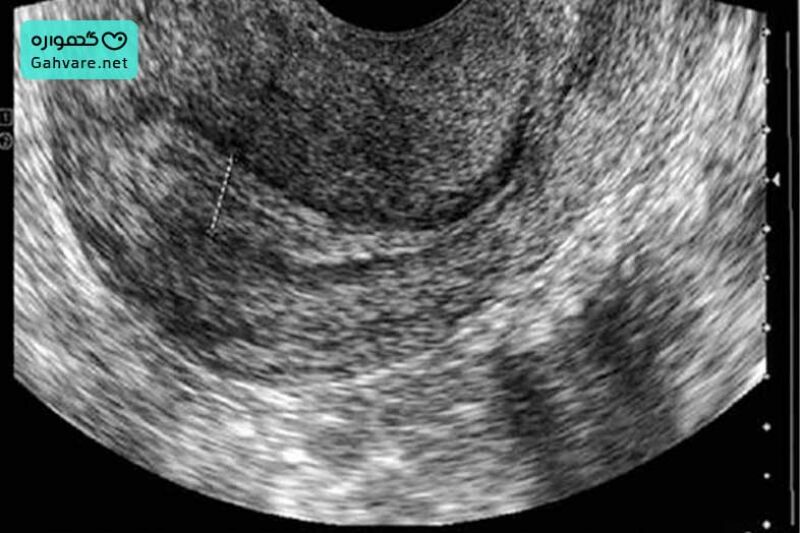

چگونه ضخامت آندومتر را اندازهگیری میکنند؟

سونوگرافی واژینال، دقیقترین و معتبرترین روش اندازهگیری ضخامت رحم مناسب برای بارداری است. دقت آن نسبت به سونوگرافی شکمی بسیار بیشتر است و معمولا پزشکان توصیه میکنند برای اندازهگیری دقیق ضخامت پوشش داخلی رحم، از این روش استفاده شود. اندازهگیری معمولا در اواخر فاز فولیکولار و روز ۱۰ تا ۱۴ چرخه قاعدگی انجام میشود. در این زمان آندومتر در بیشترین آمادگی برای لانهگزینی قرار میگیرد. در جدول زیر به ضخامت آندومتر در روزهای مختلف سیکل اشاره کردهایم:

۲- سونوگرافی

در سونوگرافی واژینال، آندومتر باید به شکل سهخطی واضح دیده شود؛ این الگو نشاندهنده رشد مناسب سلولی، پاسخ مطلوب به استروژن و خونرسانی مناسب است. اگر آندومتر یکنواخت و بدون سهخطی باشد، احتمالا هنوز برای لانهگزینی ایدهآل نیست. پزشکان معمولا با سونوگرافی، اندازه فولیکول و ضخامت آندومتر برای بارداری را ارزیابی میکنند تا بهترین زمان برای اقدام به بارداری یا انتقال جنین نیز مشخص شود.